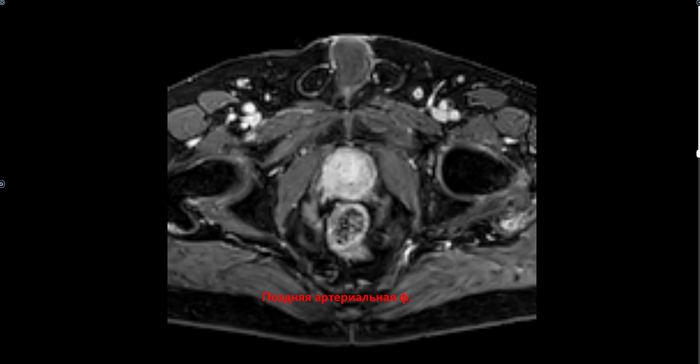

Преимущественно в периферической зоне предстательной железы, определяются участки, размерами 21х11мм,28х8мм, с 3 до 6 часов, с 6 до 11 часов условного циферблата гиперинтенсивного МР сигнала на DWI B1000,гипоинтенсивного сигнала на ИКД карте-соответствуют истинному ограничению диффузии. С быстрым накоплением контраста в раннюю артериальную фазу контрастирования, с последующим вымыванием контраста с позднюю артериальную фазу. В теле L5 позвонка -участок гипоинтенсивного сигнала на Т2 с не четкими, не ровными контурами,d 2.9см. Заключение: МР картина рака предстательной железы, V класс по PIRADS v.2.1. Участок в теле L5 позвонка наиболее соответствует mts. Состояние после троакарной цистостомии, биорхэктомии.